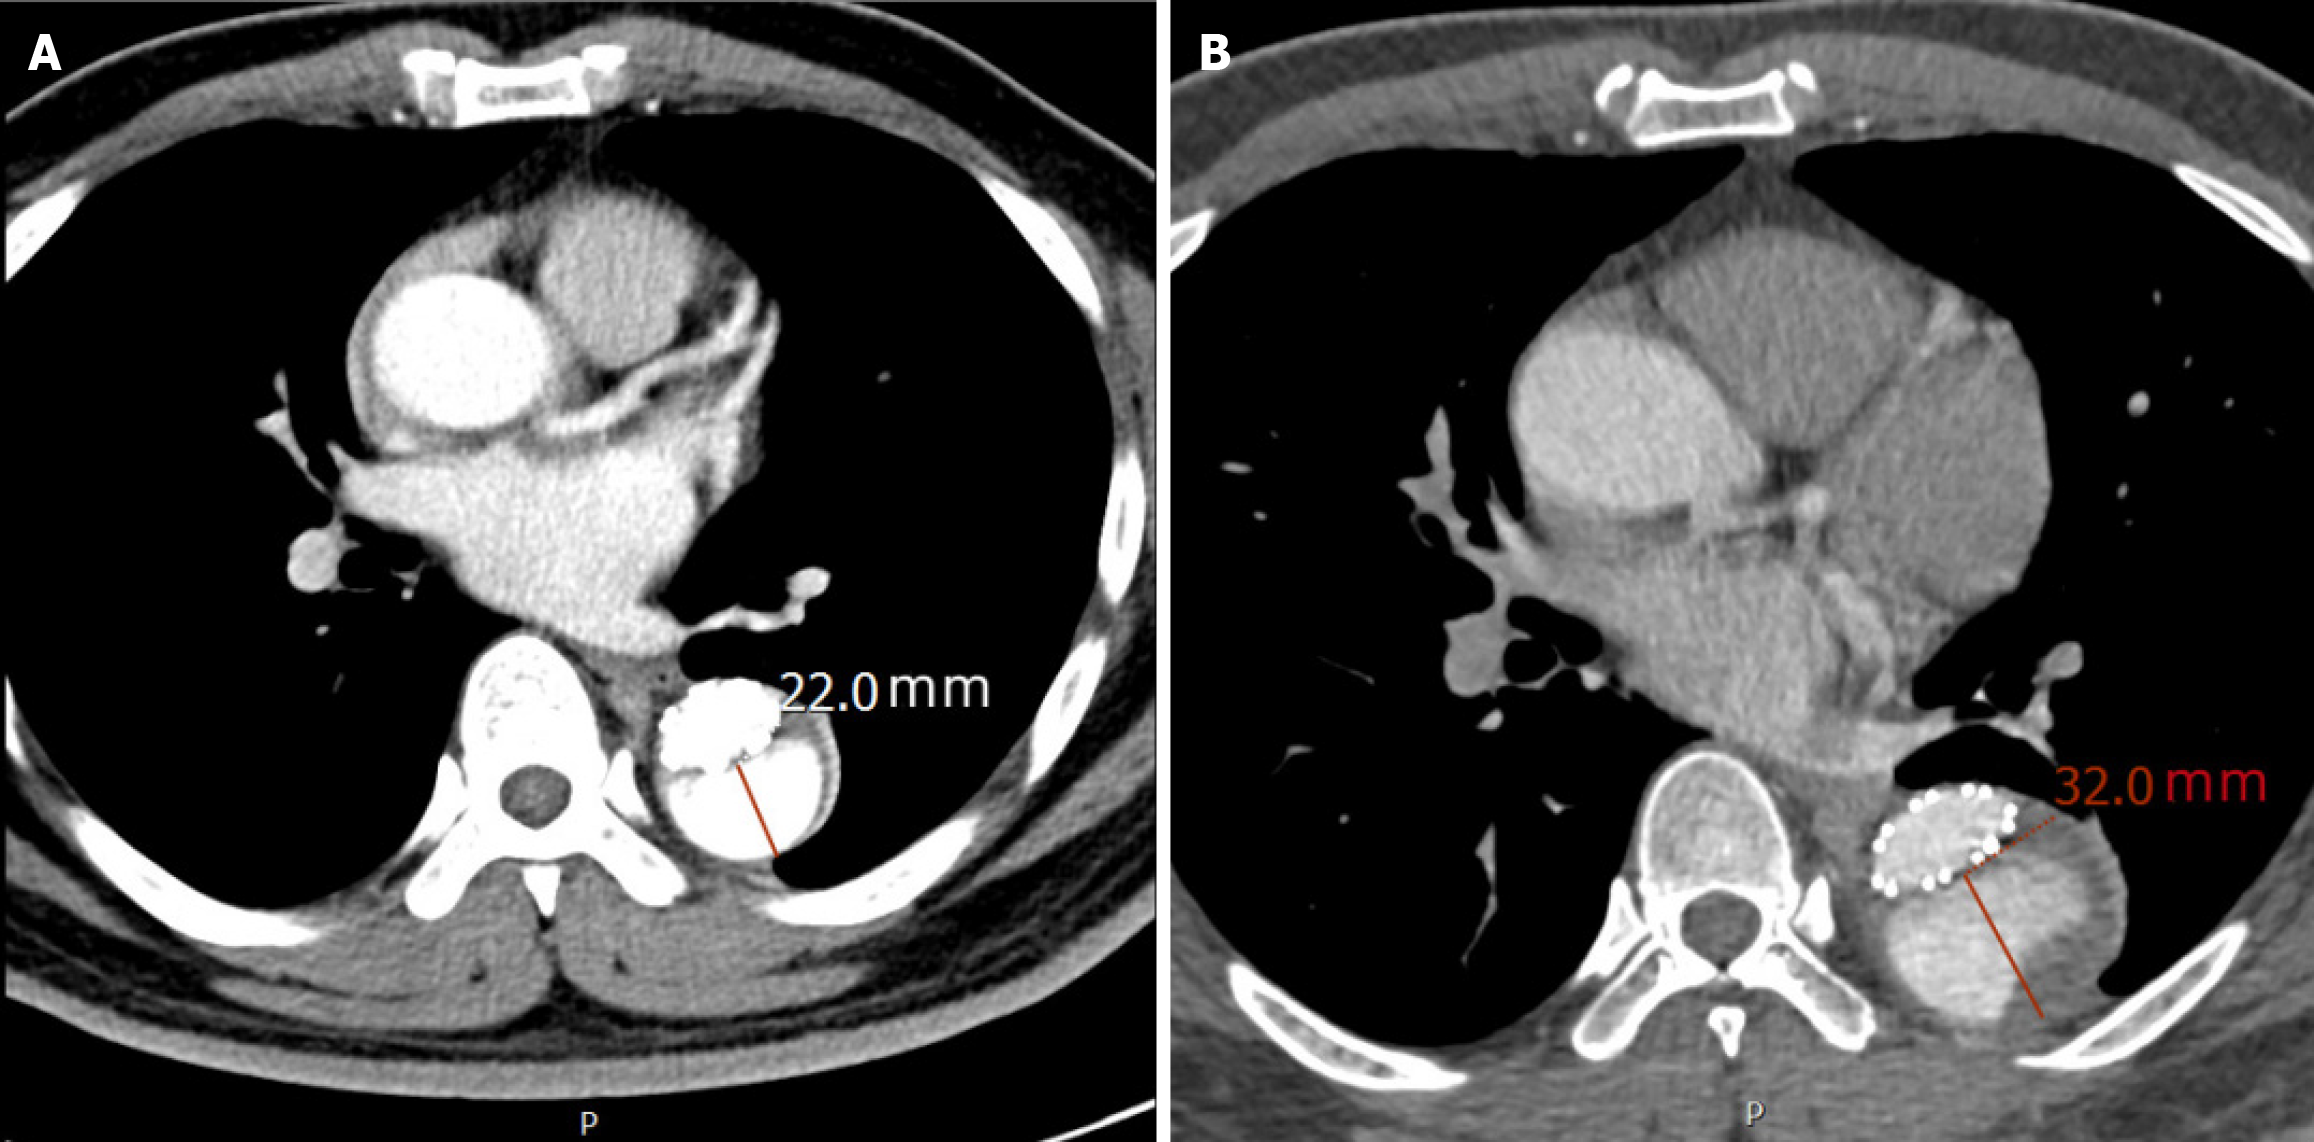

Figure 2 Representative computed tomography angiography images demonstrating aortic adverse remodeling in the same patient.

A: Post-operative computed tomography angiography (CTA) at 1 month after thoracic endovascular aortic repair (TEVAR), showing persistent perfusion within the false lumen of the aorta, with a short-axis diameter of the false lumen measuring 22 mm; B: Post-operative CTA at 6 months after TEVAR demonstrates ongoing perfusion and progressive expansion of the false lumen in the descending aorta, with the short-axis diameter increasing to 32 mm, indicative of adverse aortic remodeling.